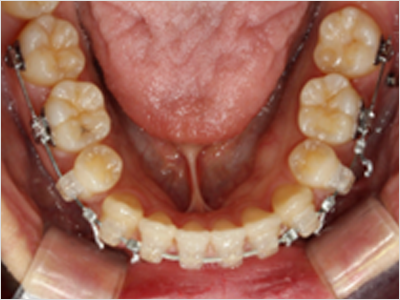

LINGUAL ORTHODONTICS

설측교정은 치아 안쪽(설측면)에 초소형 장치로 보이지 않게

아름다운 미소를 만드는 고난이도 프리미엄 교정 치료입니다.

난이도가 높은 만큼 풍부한 진료 경험이 중요합니다.

강남에서 다년간 설측교정에 특화된 경험을 바탕으로,

3D 디지털 기술을 활용한 맞춤 설계, IDBS방식을 통한

정밀하고 불편감 없는 치료를 제공합니다.

설측교정은 교정장치를 상악과 하악 모두 안쪽에 부착하는 반면,

콤비 교정은 상악은 안쪽,

하악은 바깥쪽에 부착

한다는 차이점이 있습니다.

설측교정

상악

교정장치를 안쪽에 부착

하악

콤비교정

교정장치를 바깥쪽에 부착